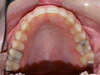

Vues après le traitement